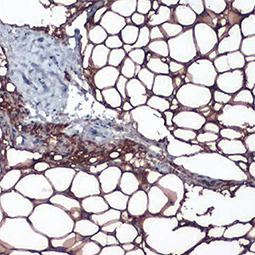

![FABP4 antibody [N3C3] FABP4 antibody [N3C3]](/upload/media/research/metabolism/Obesity/GTX116036_1.jpg)